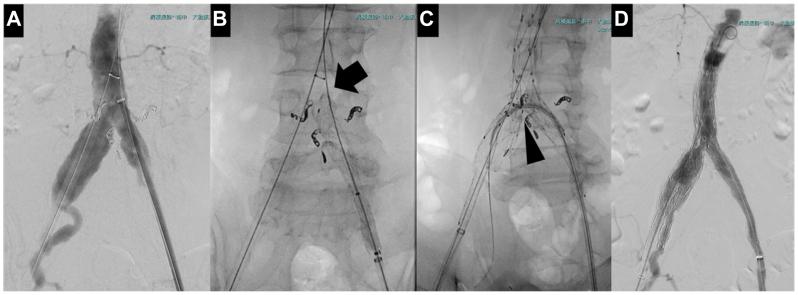

手术在全身麻醉下进行。首先采用弹簧圈栓塞腰动脉和骶中动脉;经左侧股总动脉(Common Femoral Artery, CFA)置入12Fr Dryseal 鞘管,血管造影确认腹主动脉末端位置后,于腹主动脉末端近端15mm处释放Excluder髂动脉延长器(PLC121000,W.L.戈尔公司),并使用37mm成型闭塞(Molding and Occlusion, MOB)球囊(W.L.戈尔公司)进行后扩张;经右侧股总动脉置入17Fr AFX鞘管,建立贯穿导丝以辅助AFX支架释放,血管造影确认肾动脉开口位置后,将AFX BEA22-80/20-40支架释放于Excluder髂动脉延长器上,再次使用 MOB球囊后扩张;将17Fr AFX鞘管更换为16Fr Dryseal鞘管,置入贯穿导丝准备IBE释放,确认右侧髂分叉位置后完全释放IBE;经左侧股总动脉将12Fr Dryseal鞘管送至IBE内,释放髂内动脉组件(HGB161007),并使用16mm Gekira PTA 球囊(Filmecc 公司,名古屋)后扩张;最后用MOB球囊强化AFX与IBE的重叠部位。最终血管造影未发现内漏(图 2)。手术时长114分钟,透视时长52分钟,出血量220mL,无需输血。

图2 血管造影确认腹主动脉末端位置(A);B.黑色箭头示Excluder髂动脉延长器近端边缘位于腹主动脉末端上方15mm处;C.黑色箭头示AFX支架释放于新确立的腹主动脉末端,IBE释放于该位置下方;D.术中血管造影未发现内漏